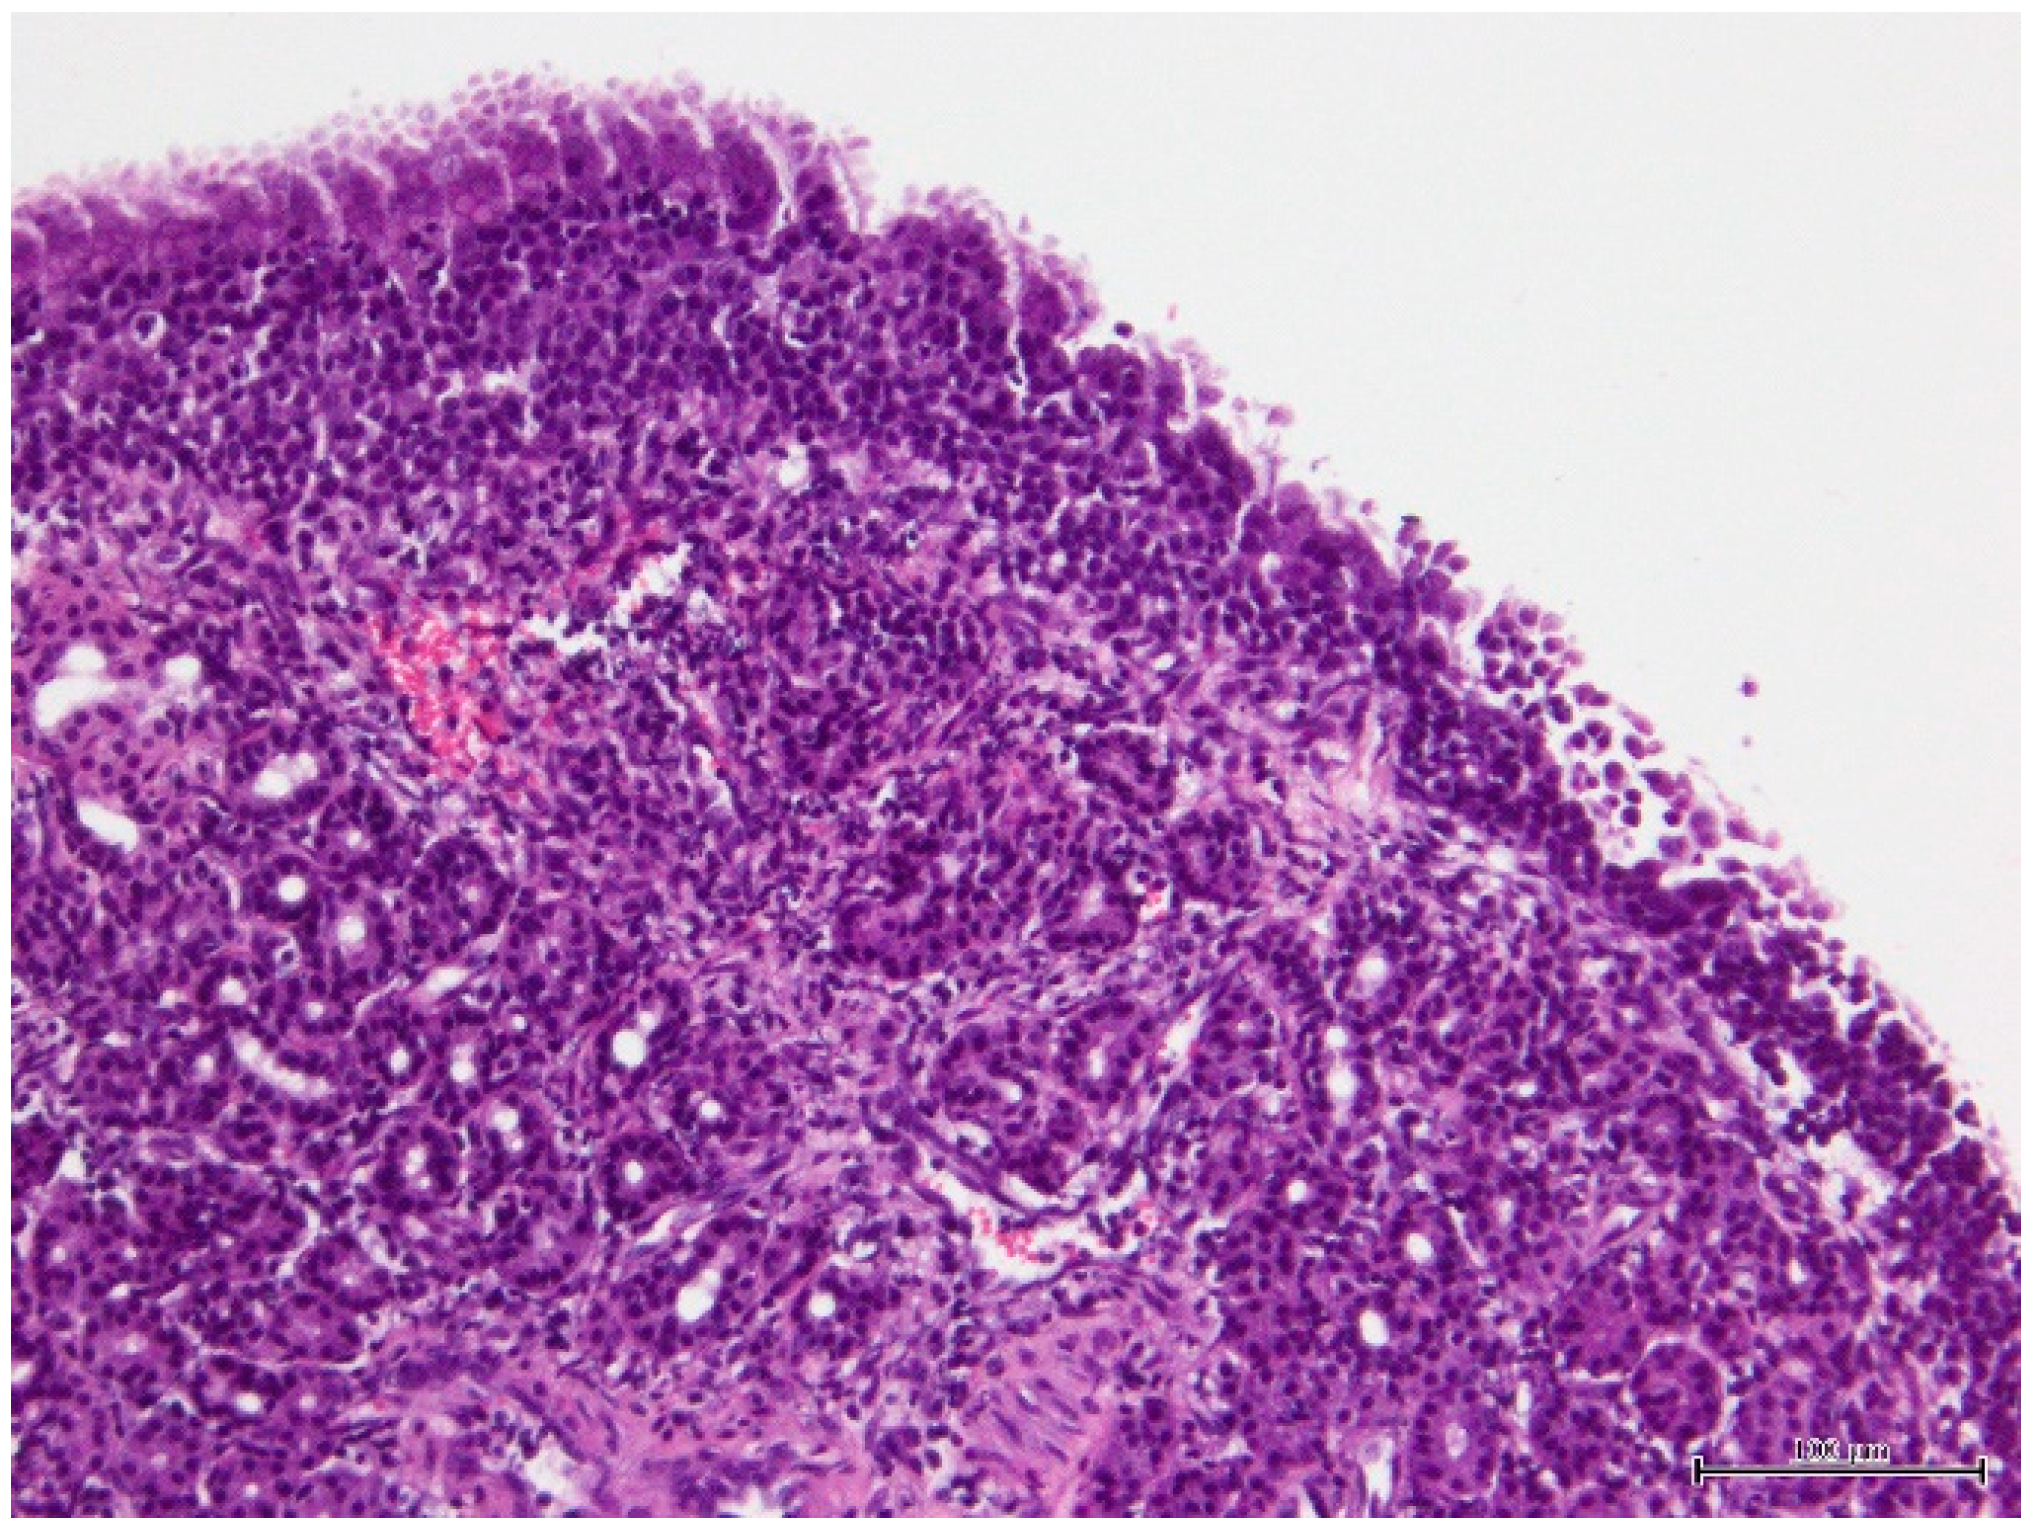

2. Case Presentation